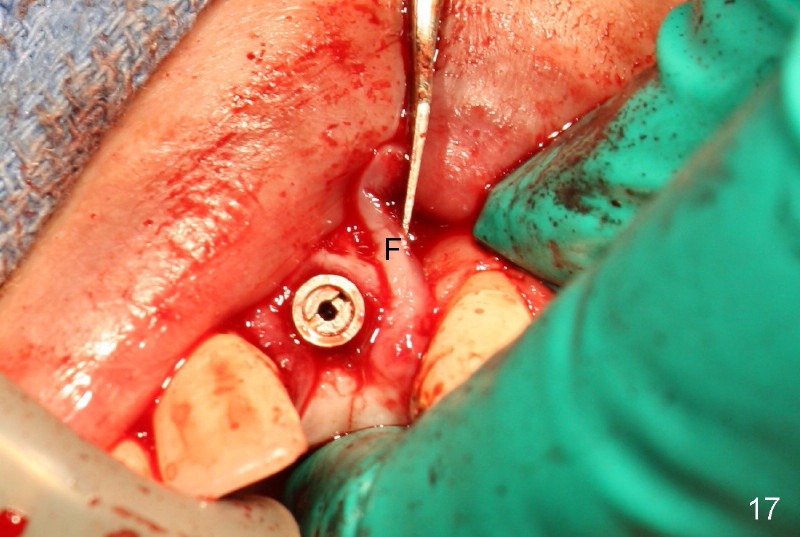

Segmental Osteotomy for Misplaced Implant

This corrective surgery was performed by Dr. Bernee Dunson.

Xin Wei, DDS, PhD, MS 1st edition 12/21/2011, last revision 12/23/2011